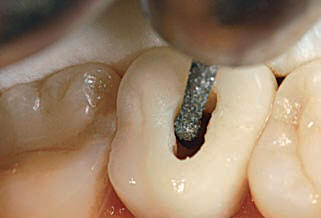

La apertura consiste en llegar a descubrir el techo de la cámara pulpar. Lo puede hacer con alta velocidad con una fresa o punta de diamante con abundante refrigeración acuosa.  Le aconsejamos que la apertura la realice con aislación relativa. Ver imagen izquierda.

La sensación al llegar a la cámara pulpar "es de caer en un vacío" ahí debe terminar la apertura propiamente dicha y debe pasar al proceso de rectificación de la cámara para el acceso a los conductos.

Usted debe rectificar las paredes y no el "Piso" de dicha cámara. Para este fin el mercado ofrece las fresas de Batt o en la actualidad la fresa Endo Z, que presentan la punta inactiva, para no producir una perforación.